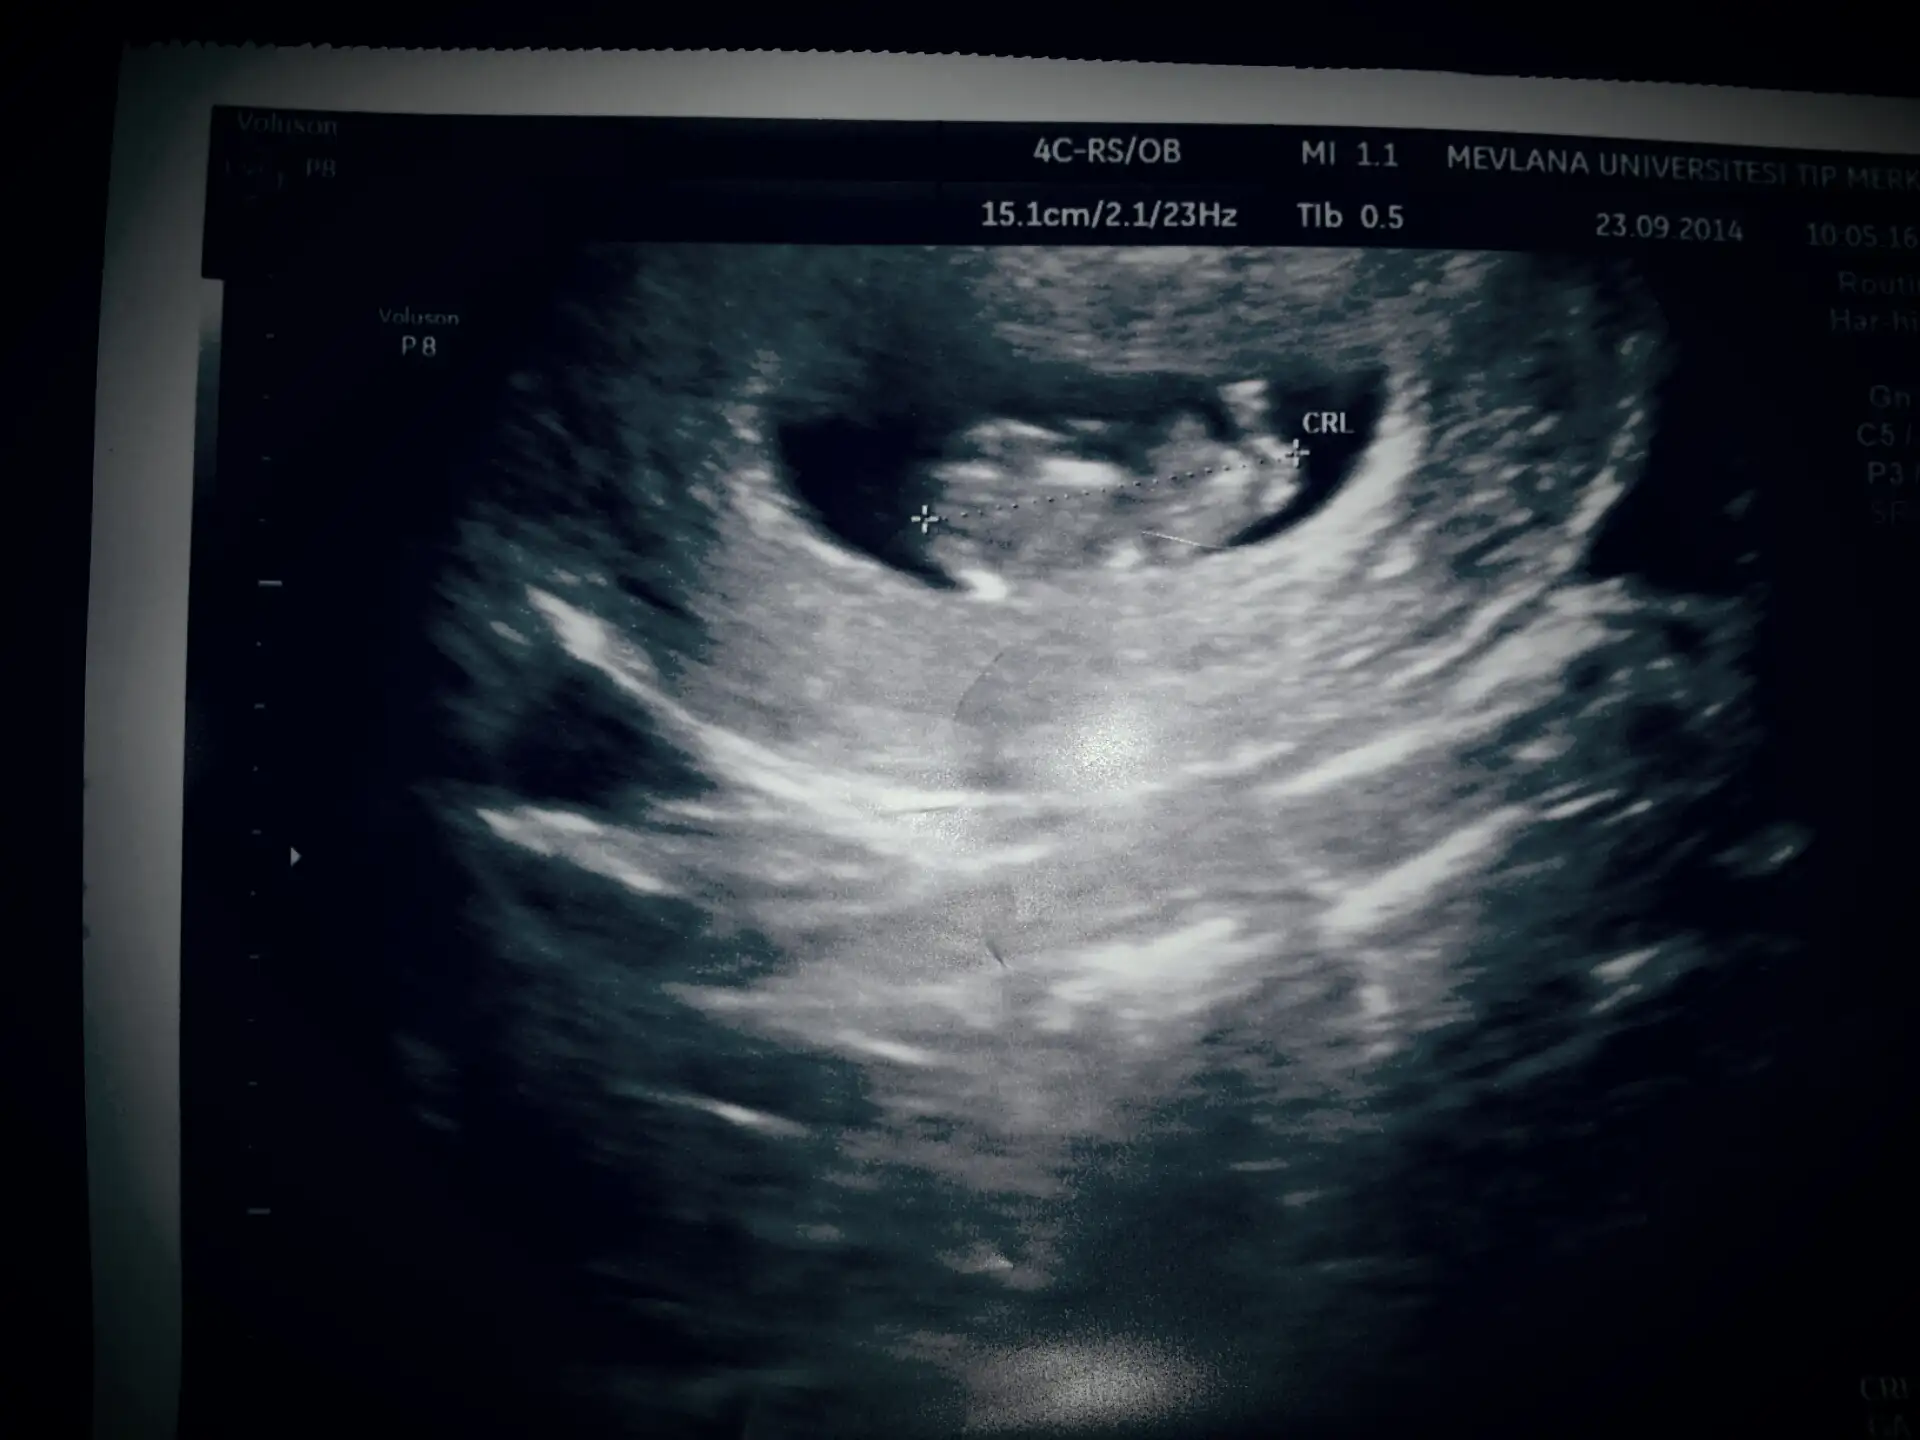

senin 10 haftalık olmuş maşaallah :)

Ben henüz keseyi ve kalp atışlarını görmediğim için kendimi pek hamile gibi hissedemiyorum

Eki Görüntüle 1252089 Canım bu benim kuzum rahatsızlanincs dün dr a gittim. Inanirmisin bazen belirti içinde bunalıyorum bazende hiç belirtin olmuyor. Her şey yolundaymis çok şükür. Darısı başına inşallah sen de görürsün gittiğinde

Ya zaten hiç gitmesen şüphe edebilirdim senden arkadaşım bak değerin süper kese görünmus o tarihe kadar beklememene çooook sevindim. Hayırlı uğurlu olsun tekrar. Tam kaç haftalık çıktın? Aklında bulursun kalp atimi olsun embriyo olsun karindan bakıldığında biraz daha geç görünür. Ben ilk alttan 6+5 de gordum kalp atışını. Sen 2 hafta sonra git git ama stres yapmadan; ) 8 haftaya kadar yolu var:)oyy maşaallah :)

Ben de dayanamadım bugün gittim doktora. keseyi gördük şükür ama kalp atışları için henüz erken dedi. 3 hafta sonra gidecekmişim.(iki hafta dayanırsam şükretsin)